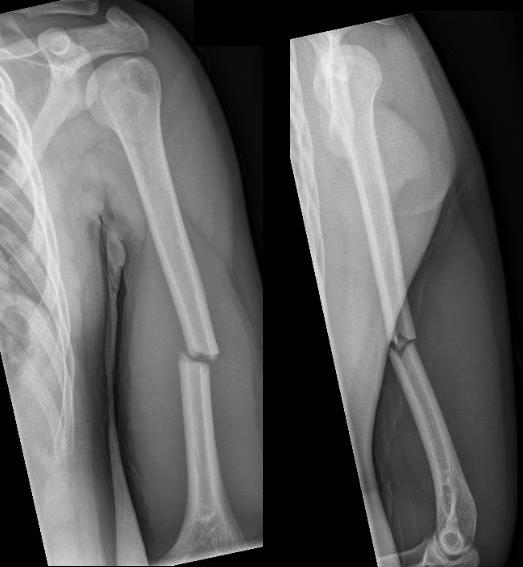

Antegrade Humeral Nail

Relative indications

Segmental fracture - need very long plate

Impending pathological fracture

Obesity

Skin compromise

Pass nail

- typically 7 mm

- ensure that nail is buried enough to protect cuff

- need to consider hardware removal

Complications

Rotator cuff pain

- must not leave nail prominent

- must carefully repair cuff